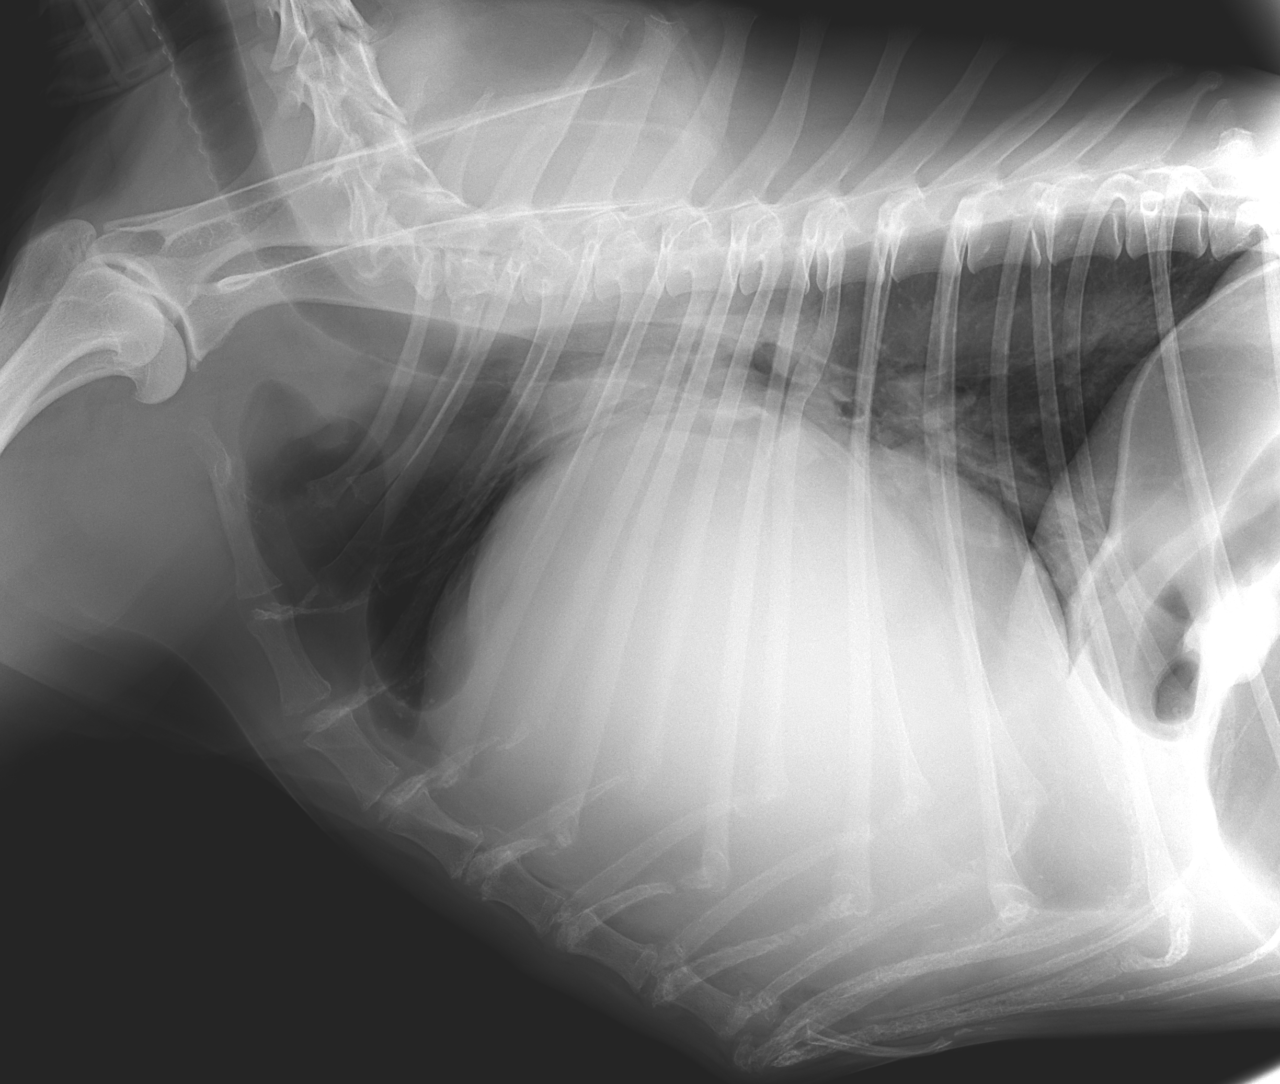

高齢(12歳)のアフガンハウンドが吐きたそうだけど、何も出てこない。次第に起立出来なくなったとのことで夜間に救急で来院しました。症状とエックス線検査から胃捻転と診断しました。また聴診時に心音は遠く、聴取出来ませんでした。胸部エックス線検査においてムーンハートが確認されました。超音波ガイドで出血性心のう水を2リットル抜去しました。バイタルサインが落ち着いたところで胃捻転整復術を実施しました。その後も出血性心のう水は貯留傾向にありました。高齢であることから血管肉腫が疑われましたが、各種画像診断においても腫瘤の存在はなくまた細胞診においても血管肉腫の可能性は低いものと判断しました。胃捻転から2週間後、心膜の生検と再発性の心膜貯留を回避する目的で心膜切除術を実施しました。心膜は顕著に肥厚し、線維化を伴っていました。病理検査の結果をもとに内科療法を併用する予定です。高齢ながら頑張ってくれました。